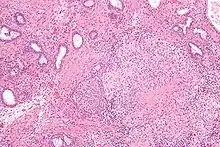

![]() Microscopic image of the Calmette–Guérin bacillus, Ziehl–Neelsen stain, magnification: 1,000nn | |